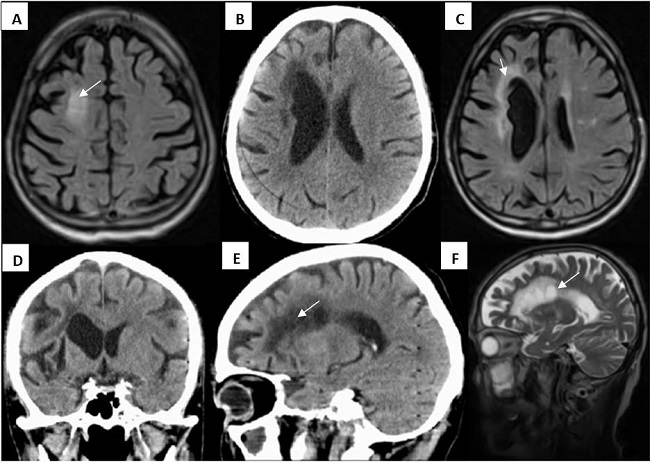

Resonancia Magnética Nuclear (RM) de Cráneo: múltiples lesiones supracallosas en centro oval con imágenes que impresionan dedos de Dawson que irradian de cuerpo calloso (Figura 2), otra mesencefálica derecha en pedúnculo y múltiples imágenes puntiformes en puente. (Figura 3) Atrofia cortical, subcortical y cerebelosa.

Múltiples enfermedades de tipo vascular pueden simular un evento desmielinizante, siendo decisivo el patrón lesional en la neuroimagen. En este caso, la RMN muestra hallazgos típicos de una vasculopatía de pequeños vasos con lesiones en sustancia blanca que predominan en distribución supratentorial frontoparietal, son pequeñas (<3mm) y se extienden más allá de la región periventricular. Además, son evidentes focos de atrofia cortical que pueden ser la huella de áreas de pequeños infartos previos. En cuanto a las lesiones infratentoriales apoya la presencia de un mecanismo vasculopático el hecho de que tienen una predilección central y el área de daño conforma el territorio clásico de distribución arterial.